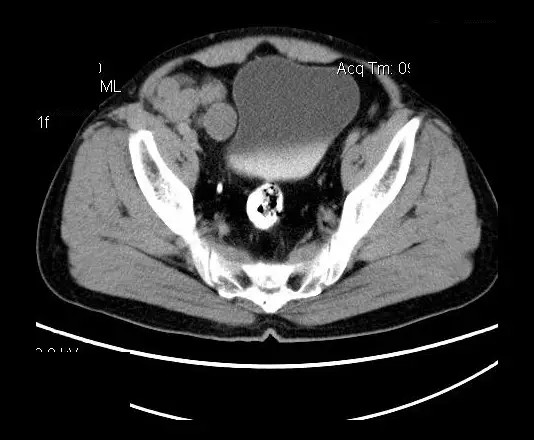

【影像表现】

盆腔右前侧及邻近腹股沟区可见多发大小不等的聚集生长的结节影,病灶呈软组织密度,边缘尚规整,分界尚清,增强扫描可见不均匀强化。膀胱局部受压,盆腔未见明显肿大淋巴结影。

平扫影像表现:Antoni A区较多病灶,在CT上呈等或略高密度影,T1WI等信号、T2WI略高信号,AntoniB区较多病灶,CT多为水样低密度、T1WI低信号、T2WI明显高信号。

增强影像表现:神经鞘膜肿瘤增强后,由于Antoni A区与B区以不同比例混合而强化不一,呈不均匀斑片状,条状强化。Antoni A 区富血供,中等或明显强化,Antoni B区乏血供,强化多不明显。